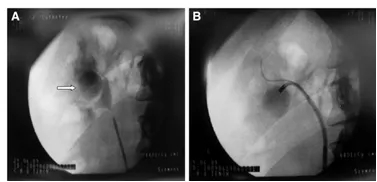

图10右侧憩室 中间部分(箭头)。b憩室处的输尿管软镜。c 亚蓝试验技术

该程序以标准 fURS 开始。一旦内窥镜进入肾盂;原则上包括通过工作通道注射造影剂在透视辅助下识别憩室颈(图 10a、b)。在操作与识别困难时,可用美蓝试验技术(图 10c)。不是单独注射对比剂,而是注射对比剂和靛蓝胭脂红的混合物。如果憩室混浊,这意味着憩室颈的特异性。然后,通过手动灌注装置,使用盐水冲洗集合系统,一旦肾盂清晰,可见蓝色从憩室颈泄漏,则可以识别憩室颈口。下一步是应用激光将憩室颈的颈口切开和随后进行结石的治疗 [56]。激光碎石术过程中,需调整好呼吸,达到精确激光碎石,激光碎石可用于上尿路尿路上皮癌、肾盂内切开术、憩室颈切口、狭窄的肾盏结石,由于呼吸和膈肌运动,可引起肾的活动度较大。因此激光碎石时是碎的是移动目标,因此操作时昼量避免损伤肾尿路上皮或肾乳头。由于这些原因,在 fURS 过程中可能需要呼吸暂停以方便治疗。最近的一份报告描述了在 fURS 期间对呼吸暂停的研究,允许其维护大约 5 分钟。这说明麻醉师和外科医生之间合作的重要性[13]。